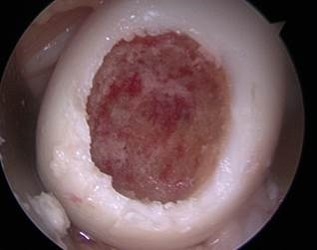

Filling of the Defect with BioCartilage

Intra-operative filling of defect with Biologic Cartilage

Second look showing healed defect